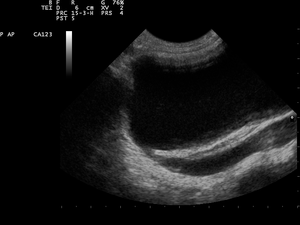

Multicystic dysplastic kidney (MCDK) is a condition that results from the malformation of the kidney during fetal development. The kidney consists of irregular cysts of varying sizes. Multicystic dysplastic kidney is a common type of renal cystic disease, and it is a cause of an abdominal mass in infants.[1]

MCDK is usually diagnosed by ultrasound examination before birth. Mean age at the time of antenatal diagnosis is about 28 weeks[7] A microscopic analysis of urine in individuals with probable multicystic dysplastic kidney should be done.[8] One meta-analysis demonstrated that unilateral MCDK occurs more frequently in males and the greater percentage of MCKD occur on the left side of the body.[9]